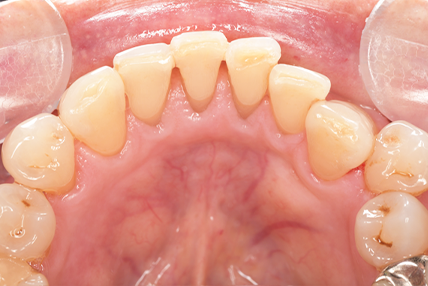

クリーニングの症例

現在の治療費と異なる場合がございます。最新の治療費は料金表をご確認ください。CASE 1

Before

After

基本情報

| 主訴 | 見た目をきれいにしたい |

| 治療期間 | 6ヶ月 |

| 治療費 | ジルコニアボンド(セラミックの被せもの)¥165,000×7(税込み) オフィスホワイトニング4回 ¥4,400×4(税込み) ホームホワイトニング¥11,000 |

| リスク・副作用 | かみ合わせがとても強い方の場合、稀に割れてしまうことがあります。 |

| 先生からの提案 | 上の前歯6本と右下の2番目の歯はセラミックの被せもので治療。 残りの下の前歯5本はプラスチックの材料で虫歯を治療し、 ホワイトニングをおこないました。白くなったご自身の歯の色に合わせてセラミックの 被せものを作成しています。 模型上で完成後をシュミレーションし、上の歯茎の位置をきれいに見えるように 揃えています。(外科処置はしていません) |